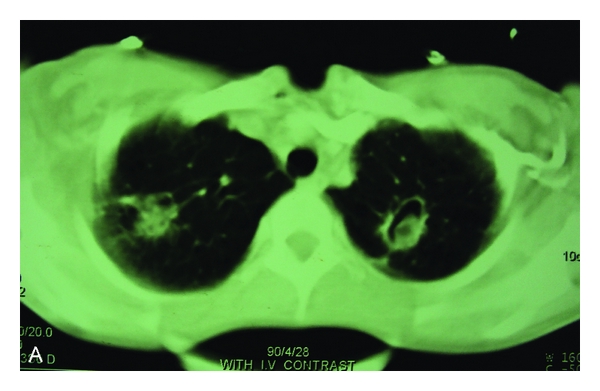

The thorax CT scan was performed and showed biapical cavitary lesions and intracavitary soft tissue projection in the left lung. Also scattered nodular infiltration with a large mass-like consolidation was seen in the right lower lobe. Right hilar and subcarinal adenopathy there also reported (Figure 1).

Bronchoscopy was done which showed a necrotic obstructive mass at the right middle bronchus. No bacterial or fungal agents were isolated from sputum and bronchoalveolar lavage (BAL) fluid. Histopathological study showed filamentous septated hyphae with acute angle branching, without any evidence of granuloma or necrotizing vasculitis. Galactomannan assay index of serum was highly positive (10 ng/mL). Voriconazole was added to her treatment.